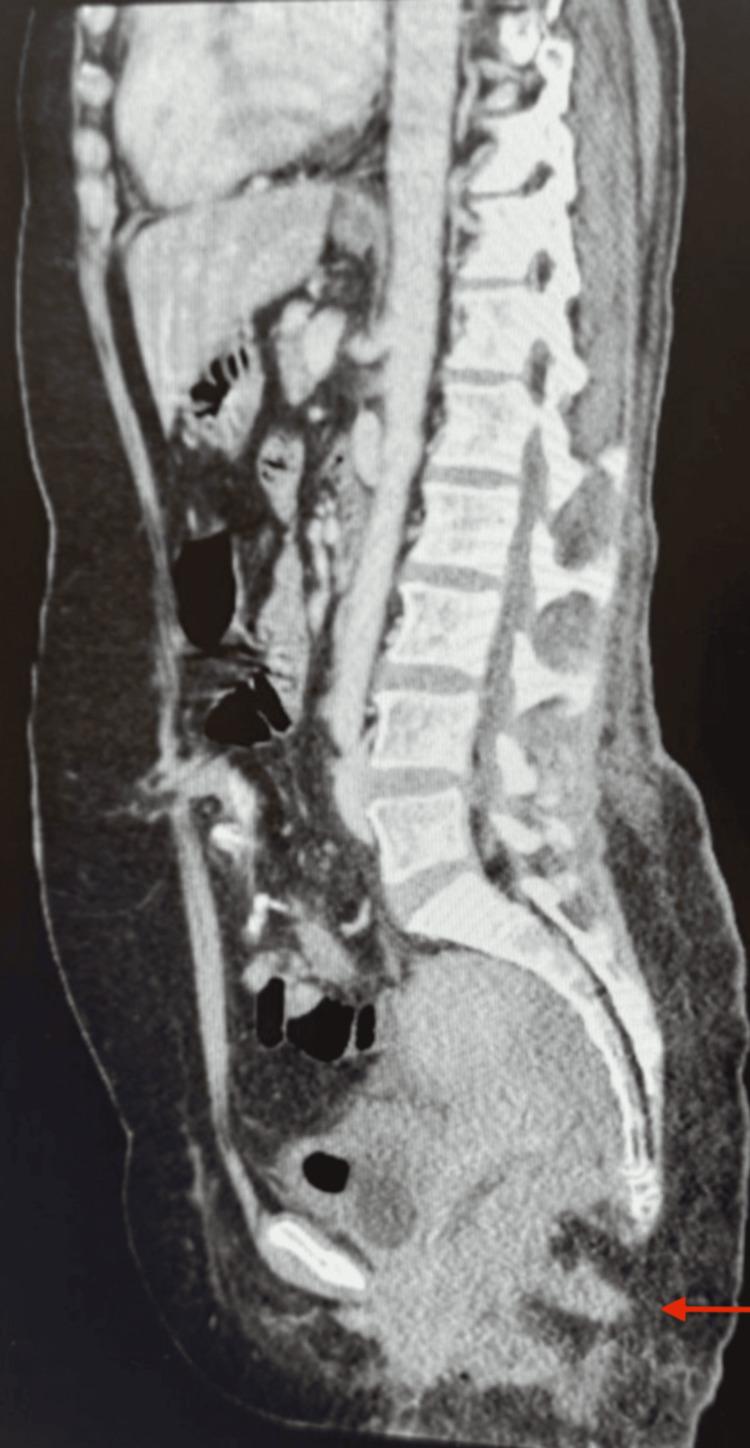

This case report discusses a 56-year-old Saudi female patient diagnosed with extramammary Paget's disease (EMPD) affecting the perianal region. Initially presenting with a one-year history of perianal itching and erythematous plaques, she underwent multiple evaluations, including a punch biopsy that revealed atypical epidermal infiltrates suggestive of EMPD or squamous cell carcinoma in situ. Comprehensive imaging and additional biopsies confirmed the diagnosis and assessed the extent of the disease. The patient underwent laparoscopic sigmoid colostomy and a wide local excision, followed by reconstructive procedures involving multidisciplinary surgical teams. Postoperative pathology confirmed perianal Paget's disease (PPD) with positive resection margins at the proximal vaginal area. The patient was discharged in stable condition and continues to receive follow-up care, highlighting the importance of multidisciplinary management in complex cases of perianal premalignancies and malignancies. Notably, to the best of our knowledge, no other case report has addressed a lesion of this size. Additionally, the initially uncertain location of the primary cancer lesion further distinguishes our case. Further studies are warranted to monitor for disease recurrence and evaluate the need for additional interventions.

本病例报告讨论了一名56岁的沙特女性患者,她被诊断患有累及肛周区域的乳房外佩吉特病(EMPD)。该患者最初表现为肛周瘙痒和红斑性斑块,病程长达一年,她接受了多项评估,包括一次穿刺活检,结果显示非典型表皮浸润,提示为EMPD或原位鳞状细胞癌。全面的影像学检查和额外的活检确诊了病情并评估了疾病的范围。患者接受了腹腔镜乙状结肠造口术和广泛局部切除术,随后由多学科手术团队进行了重建手术。术后病理证实为肛周佩吉特病(PPD),近端阴道区域切缘阳性。患者出院时情况稳定,并继续接受随访护理,这凸显了多学科管理在肛周癌前病变和恶性肿瘤复杂病例中的重要性。值得注意的是,据我们所知,没有其他病例报告涉及如此大小的病变。此外,原发性癌灶最初位置不确定这一点也使我们的病例与众不同。有必要进行进一步研究以监测疾病复发情况并评估是否需要额外干预措施。